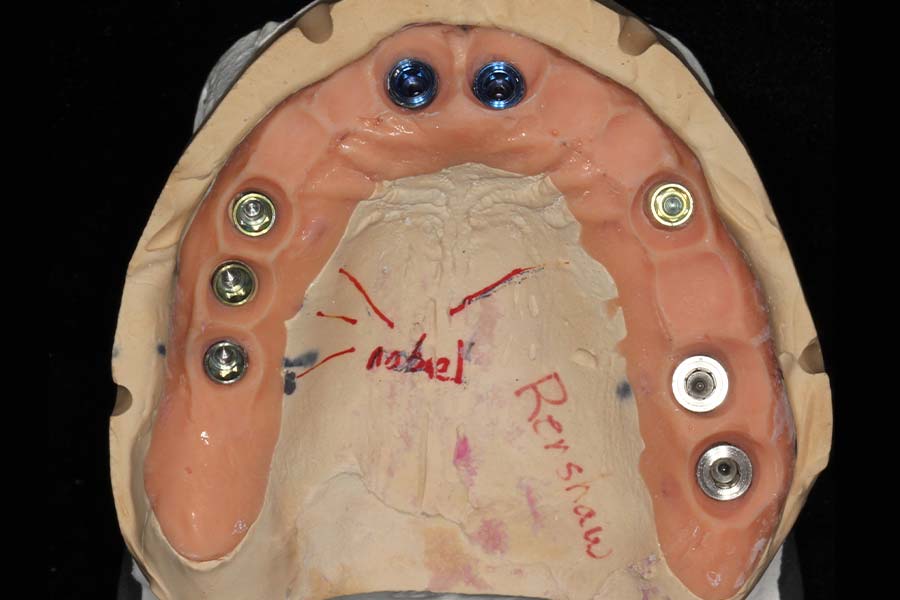

Smile GalleryImplant RestorationsFull Mouth Implant Restoration Full arch zirconia implant bridge (full smile) 1 of 37 Pre-op full smile Pre-op lips retracted Pre-op panoramic x-ray Extraction of strategic teeth Placement of implants Extraction of some remaining teeth after verification of adequate implant stability Occlusal view Post-op panoramic x-ray Immediately fabricated provisional restoration (tissue side view) Immediately fabricated provisional restoration (occlusal side view) Immediate provisional delivered on day of surgery Immediate provisional 2 weeks later Scalloped tissue developed from the provisional at 2 weeks Jig used for making a master impression Provisional in place (full smile) Provisional in place (lips retracted) Provisional in place (right side) Provisional in place (left side) Wax try-in (full smile) Wax try-in (right side full smile) Wax try-in (left side full smile) Wax try-in (full face, lips together) Wax try-in (full smile) Wax try-in (right side) Wax try-in (left side) Wax try-in (lips retracted) Full arch zirconia implant bridge on master cast (frontal view) Full arch zirconia implant bridge on master cast (occlusal view) Implant positions and soft tissue representation on master cast (occlusal view) Soft tissue representation on master cast (frontal view) Full arch zirconia implant bridge (tissue side view) Soft tissues on day of delivery (occlusal view) Soft tissues on day of delivery (frontal view) Full arch zirconia implant bridge delivered (lips retracted) Full arch zirconia implant bridge (lips retracted, close up) Post treatment panoramic x-ray Full arch zirconia implant bridge (full smile)